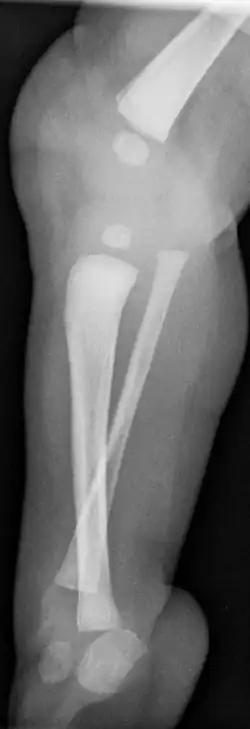

Eine Tibiale Hemimelie oder ein Tibialer Längsdefekt bezeichnet das angeborene Fehlen (Aplasie) oder die Unterentwicklung (Hypoplasie) der Tibia. Sie kann isoliert, häufiger aber in Verbindung mit Fehlbildungen am Fuß medial sowie einer Varusstellung im Rückfuß einhergehen.[1]

- Typ II Tibia nur distal fehlend, Artikulation zum Femur erhalten

Je nach Ausmaß des Fehlens der Tibia kniegelenksnahe besteht eine Kniebeugekontraktur und verminderte Aktivität der Oberschenkelstreckmuskulatur.[5]

Bereits im Mutterleib kann während einer Ultraschalluntersuchung die Fehlbildung erkannt werden,[2] die Verkürzung und Fehlstellung des Unterschenkels ist nach der Geburt offensichtlich. Ein Röntgenbild kann das Ausmaß der Fehlbildung sowie zusätzliche knöcherne Veränderungen dokumentieren. Mittels Sonographie können die knorpeligen Anlagen und deren Stellung zum Gelenk sicher dargestellt werden, wesentlich bei den Typen II und III.

- Typ II: Zur Stabilisierung des Kniegelenkes Verbindung des distalen Tibiaanteiles an die Fibula.[1]